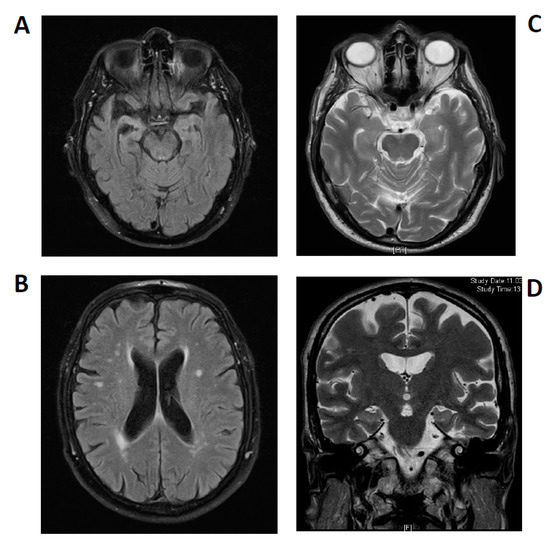

Figure 2.

Brain magnetic resonance imaging. Patient 1: Asymmetrical atrophy of mesiotemporal structures in the right hemisphere and leukoencephalopathy (A,B): T2-weighted fluid-attenuated inversion recovery (FLAIR). Patient 2: Arachnoid cyst paramedial in posterior skull, but no further pathology (C,D) T2-weighted sequences).

His MRI dataset was reviewed in the Department of Neuroradiology, confirming an asymmetrical atrophy of the mesiotemporal and right temporopolar brain regions and progressive leukoencephalopathy in white matter (Figure 2A,B). MRI data were initially compared to those obtained in 2014 that had shown no atrophy and fewer white matter lesions. The mesiotemporal atrophy was interpreted as being compatible with a limbic encephalitis at later stages, which was recently reported in courses of limbic encephalitis by Wagner et al. [19].

Autoantibody analysis via immunofluorescence testing (due to his tumor history) as an indicator for possible underlying autoimmunity led us to detect KCNA2 autoantibodies in serum. CSF analysis 5 months later in 2020 revealed no specific autoantibodies against neural and intracellular antigens, but elevated markers of neuronal degeneration such as an elevated S100 (4.1 µg/L (pathological > 2.7 µg/L), neuron-specific enolase (35 ng/mL (pathological >30 ng/mL) and tau protein (505 pg/mL (>450 pg/mL) and a reduced ratio of Aß42/40 (0.38 (pathological ˂ 0.5). KCNA2 autoantibodies were again detected in serum 5 months after their first detection in 2020. Neuroborreliosis and lues were excluded by CSF diagnostics (Table 1). A cranial MRI 2 months after his initial presentation in 2020 revealed cerebral microangiopathy and an arachnoid cyst left paramedial in the occipital lobe, but no signs of an encephalitis (Figure 2C,D). We initiated a single course of high-dose intravenous methylprednisolone and continued rivastigmine.

In patient 1, we described a pattern of persistent cognitive impairments ascertained through comprehensive neuropsychological assessment. His cognitive decline’s subacute onset, and the discovery of additional mood and psychotic symptoms made us suspect an autoimmune pathology, especially because of the presence of serum autoantibodies against the Kv1.2 subunit. MRI brain-images were reviewed by our neuroradiological colleagues, who confirmed the asymmetrically atrophied mesiotemporal structures as being compatible with a post-acute phase of a limbic encephalitis. A progressive reduction in hippocampal structures in the subacute stadium of limbic encephalitis was shown systematically by Wagner et al. in autoimmune-related limbic encephalitis [19]. Furthermore, in the course of limbic encephalitis, the initial swelling of hippocampal structures can be followed by their atrophy, as in the present case [20]. Progressive leukoencephalopathy in white matter was found to be compatible with demyelination or inflammation defining a possible autoimmune encephalitis, but that does not fulfill the criteria defining a definitive limbic encephalitis, which requires such alterations restricted to the medial temporal lobe [21]. In a recent position paper we emphasized that an autoimmune etiology of psychiatric syndromes including cognitive impairment is conceivable [22] despite not fulfilling the criteria for autoimmune encephalitis [23]. Current consensus articles addressing how to specify a definitive limbic encephalitis reported that at least four criteria must be met (namely, a typical subacute onset of clinical symptoms, the aforementioned bilateral MRI abnormalities, and an abnormal EEG or pathological CSF parameters and careful exclusion of alternative causes) [21,23,24] in combination with the detection of now-established antibodies against neural surface antigens or onconeural antibodies [24]. In light of the hippocampal atrophy detected here and Prüss et al. [23], we diagnosed a possible autoimmune encephalitis due to Graus criteria [21].

The atypical presentation of progressive and fluctuating cognitive impairments in conjunction with hypoesthesia, thermohypoesthesia and dysphagia, and the patient’s tumor history prompted us to take a diagnostic approach seeking potential autoimmunity in the second patient’s course, as did recently published criteria [22]. Indeed, in patient 2 we discovered KCNA2 autoantibodies corroborated by repeated measurements, and, as in patient 1, patient 2’s antibodies were restricted to serum probes. It is noteworthy that our CSF analysis revealed elevated total tau and phospho-tau 181 concentrations, which indicate axonal neurodegeneration. Furthermore, the coincidence of a reduced ß amyloid 1–42/1–40 ratio in CSF implied Alzheimer’s disease. Unlike in neurodegenerative diseases, subsequent brain MRI imaging revealed no mesiotemporal atrophy, but neither were there any specific indications for encephalitis like hyperintense lesions in mesio- and extra-temporal brain structures. Summarizing the results of CSF analyses and affection of episodic memory functions at time of onset, we discussed this case in the context of Alzheimer’s disease. According to findings by Lang et al. [14], Kv1.2 autoantibodies are likely arising secondary to diverse pathologies setting free the intracellular epitope of Kv1.2, then rendered accessible to the immune system. They stated that the primary pathological insult may not be immune. However, uncertainty remained in the presence of the KCNA2 autoantibodies, as autoimmune-mediated dementia seemed possible according to recently published criteria [22] and fluctuating cognitive deficits are known to be an indicator of a possible autoimmune dementia involving immunotherapeutic responsiveness [25]. Some authors have hypothesized that evidently elevated total tau in CSF may be associated with secondary neurodegeneration due to CNS inflammation. This mechanism was recently discussed, and CSF biomarkers of neurodegeneration have proven to correlate inversely with clinical improvement [26,27]. A potential association between autoantibodies and cognitive decline in autoimmune dementia has been thoroughly investigated, and currently recruiting clinical trials investigating the impact of immunotherapy in suspected Alzheimer’s disease associated with novel autoantibodies have been reviewed elsewhere [28,29]. Autoantibodies exhibit variable associations with paraneoplastic syndromes sometimes resembling neurocognitive syndromes such as Alzheimer’s disease, which we had to reconsider as the second patient had a positive tumor history. Actually, both men had a potential paraneoplastic background indicated by their medical history and the diagnostic findings (first patient’s). From this viewpoint, unlike well-established neuronal cell-surface antibodies (e.g., LGI1 or CASPR2), KCNA2 autoantibodies may not necessarily interfere with extracellular protein functions, but they do represent a more potential surrogate marker of a paraneoplastic neurological syndrome. Interestingly, Lang et al. recently reported paraneoplastic neuromyotonia and Lambert Eaton syndrome, both possibly related to Kv1 subunit reactivity in small-cell lung carcinoma. Unfortunately, as both patients have been lost to follow up, we have no information on further tumor diagnostics or their response to immunotherapy. Intravenous corticosteroids appeared to improve speech fluency and attention functions in the first patient, but we could not confirm this as he refused to undergo a consecutive neuropsychological assessment. We think it is probable that also non-anti-inflammatory effects, e.g., psychotropic effects, could have caused the improvement in his case. In the light of the aforementioned reports, follow-up diagnostics would undoubtedly be helpful, as there is evidence of alleviated cognitive impairments in conjunction with autoimmune dementia [25].